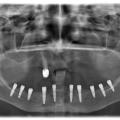

Установка 10 имплантантов на беззубую челюсть с помощью компьютерной программы: Через месяц после удаления

Через месяц после удаления